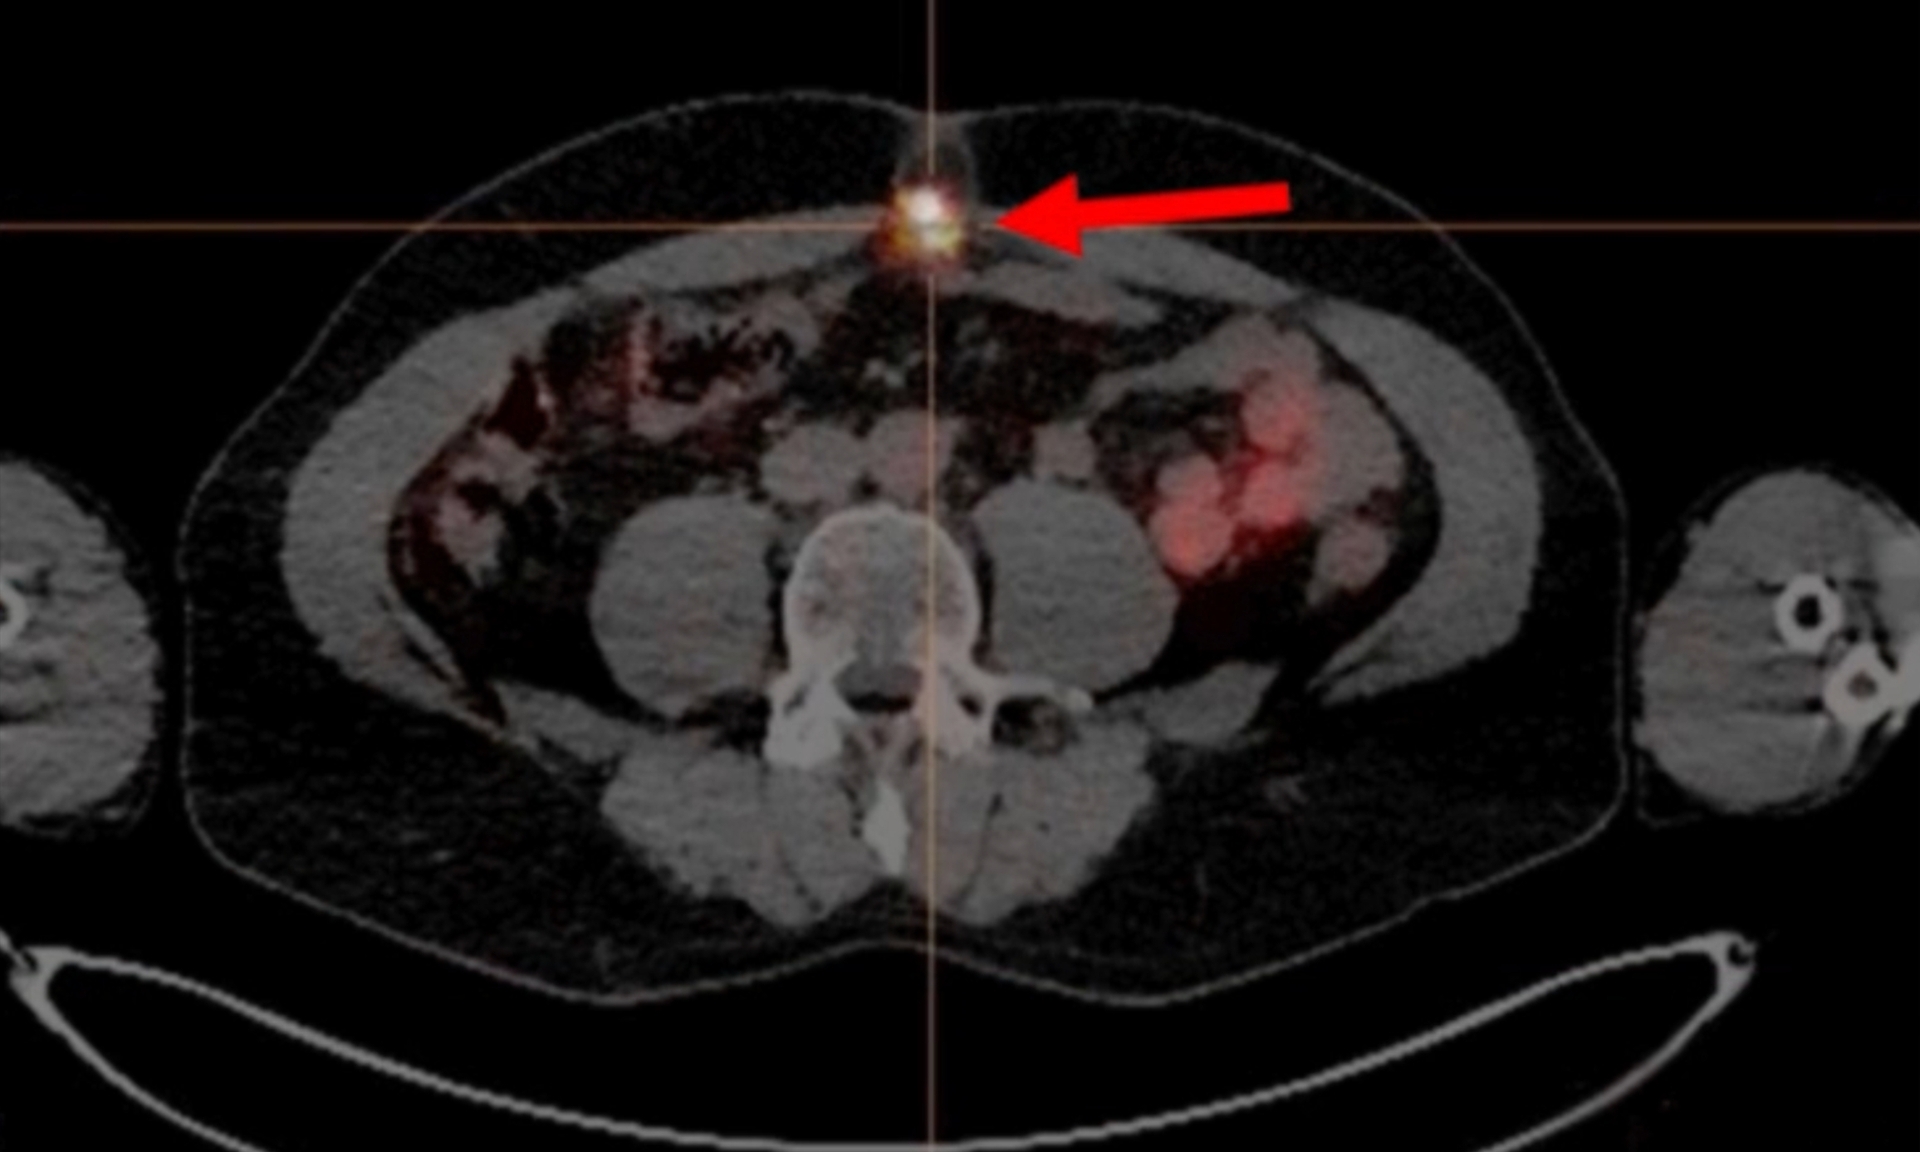

161 Terbium-PSMA Radioligand Therapy in Prostate Cancer Brain Metastases

The following clinical case illustrates two important aspects of radioligand therapy in prostate cancer treatment. First, it is a highly effective approach capable of transforming the disease from potentially lethal to a manageable chronic conditio

Therapy Response After Combined CyberKnife & PSMA Radioligand Therapy

3x 177Lu-PSMA and 1x 161Tb-PSMA, at 4-Week IntervalsMr. J. Low, 67 years old, was first diagnosed with prostate cancer in February 2011. After multiple prior treatments, including primary external beam radiation, ADT, ARPI, three cycles of immunoth